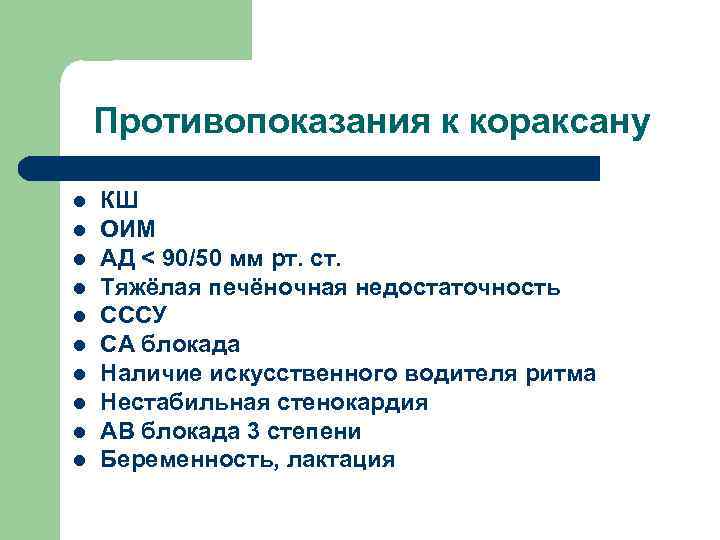

Противопоказания к кораксану l l l l l КШ ОИМ АД < 90/50 мм рт. ст. Тяжёлая печёночная недостаточность СССУ СА блокада Наличие искусственного водителя ритма Нестабильная стенокардия АВ блокада 3 степени Беременность, лактация